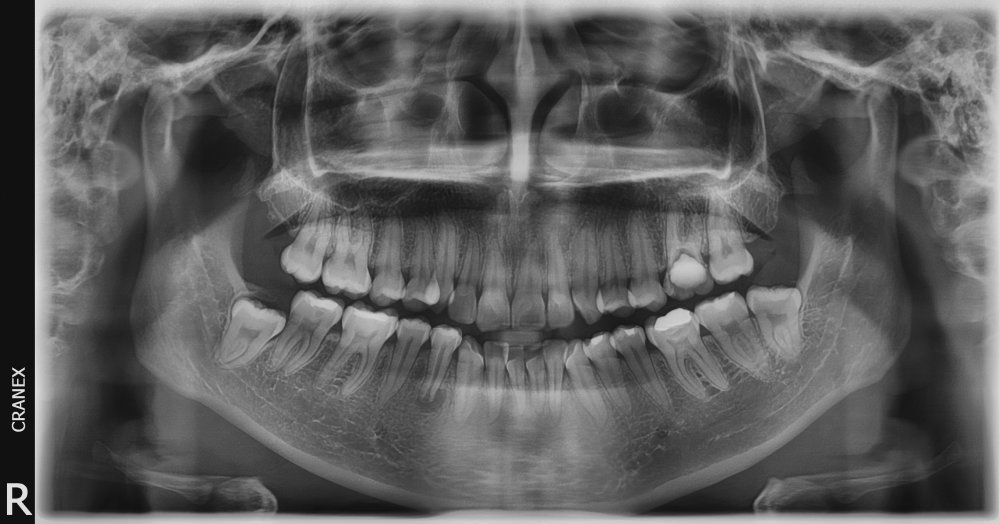

- RX.Panorámica